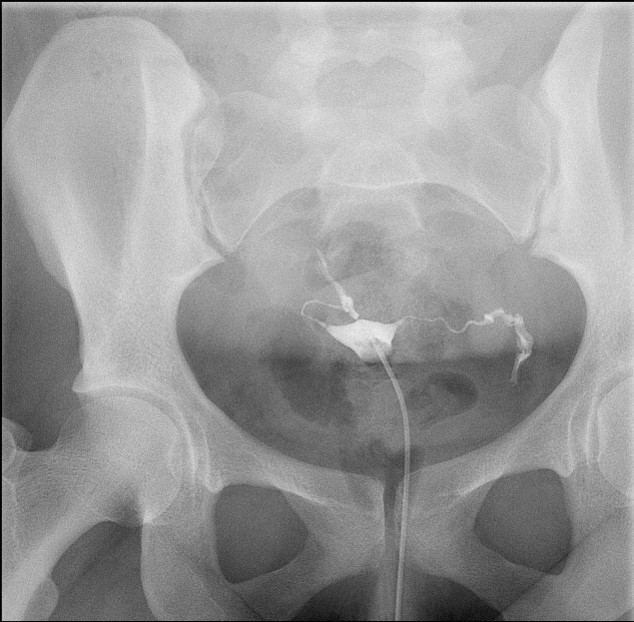

- The gynecologist will begin injecting contrast material into the uterus. Obtain images periodically throughout the procedure (usually at the direction of the gynecologist). The images should include the uterine cavity filled with contrast material, bilateral fallopian tubes filled with contrast material, and spillage and dispersion of contrast material into the peritoneal cavity (image 1) (image 2) (image 3) (image 4) (image 5).